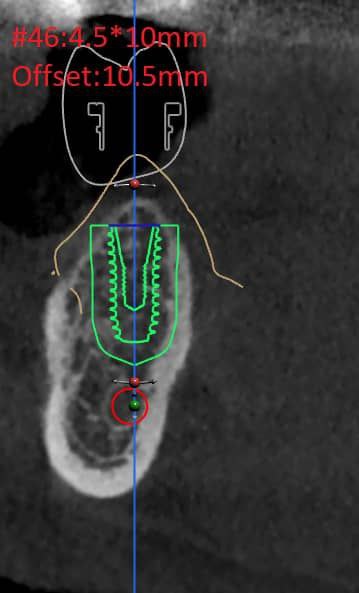

تصویربرداری سه بعدی( CBCT):

اسکن سه بعدی فک و دندان ها انجام میشود تا ساختارهای دقیق استخوان و موقعیت عصب ها مشخص شود

طراحی دیجیتال:

با استفاده از نرمافزارهای پیشرفته، محل قرارگیری دقیق ایمپلنت طراحی و شبیه سازی میشود

ساخت راهنمای جراحی( Guide surgical):

با پرینتر سه بعدی ابزار خاصی تولید میشود که به جراح کمک میکند ایمپلنت را با دقت بسیار بالا در جایگاه مناسب قرار دهد